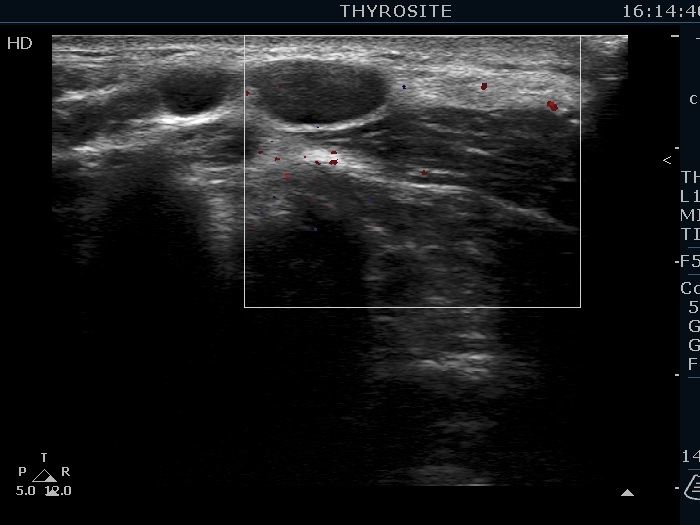

Above and lateral to the left lobe, transverse scan, color Doppler mode. This mass is also avascular.